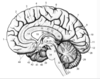

Key gyri on the lateral surface of the frontal lobe

Superior frontal gyrus

Middle frontal gyrus

Inferior frontal gyrus (pars triangularis, pars orbitalis, pars opercularis)

Precentral gyrus

Key sulci on lateral surface of frontal lobe

Superior frontal sulcus

Inferior frontal sulcus

Pre-central sulcus